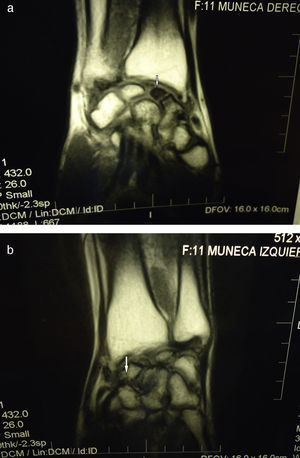

La radiografía de los carpos mostró rarefacción ósea en ambos escafoides, con esclerosis marcada y fenómenos degenerativos graves (fig. 1), lesión que se confirmó en la resonancia magnética (RM). Estos hallazgos eran compatibles con osteonecrosis (ON) bilateral de dicho hueso, por lo que se realizó diagnóstico de enfermedad de Preiser bilateral idiopática, al no encontrarse patología asociada (fig. 2A y B).

A) RM imagen coronal T1WI (TR 432, TE 26). Fractura del escafoides derecho con necrosis del fragmento proximal, marcadamente hipointenso (flecha), con cambios degenerativos crónicos por inestabilidad. B) RM imagen coronal T1WI (TR 432, TE 26). Fractura del escafoides izquierdo, sin consolidación ni cambios en el patrón de señal del fragmento proximal, con cambios degenerativos crónicos por inestabilidad (flecha).